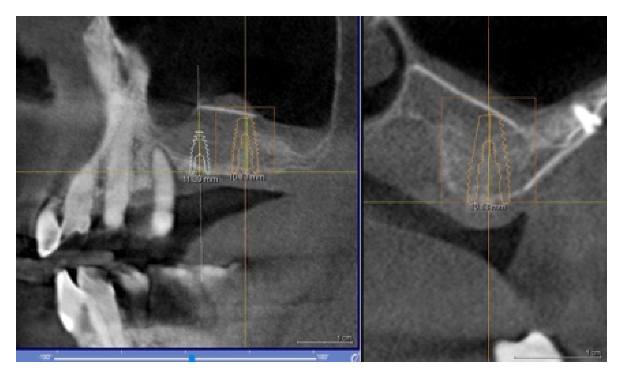

4.1. Clinical Case n.1.

4.2. Clinical Case n.2.

4.3. Clinical Case n.3.

4.4. Clinical Case n.4.

4.5. Clinical Case n.5.